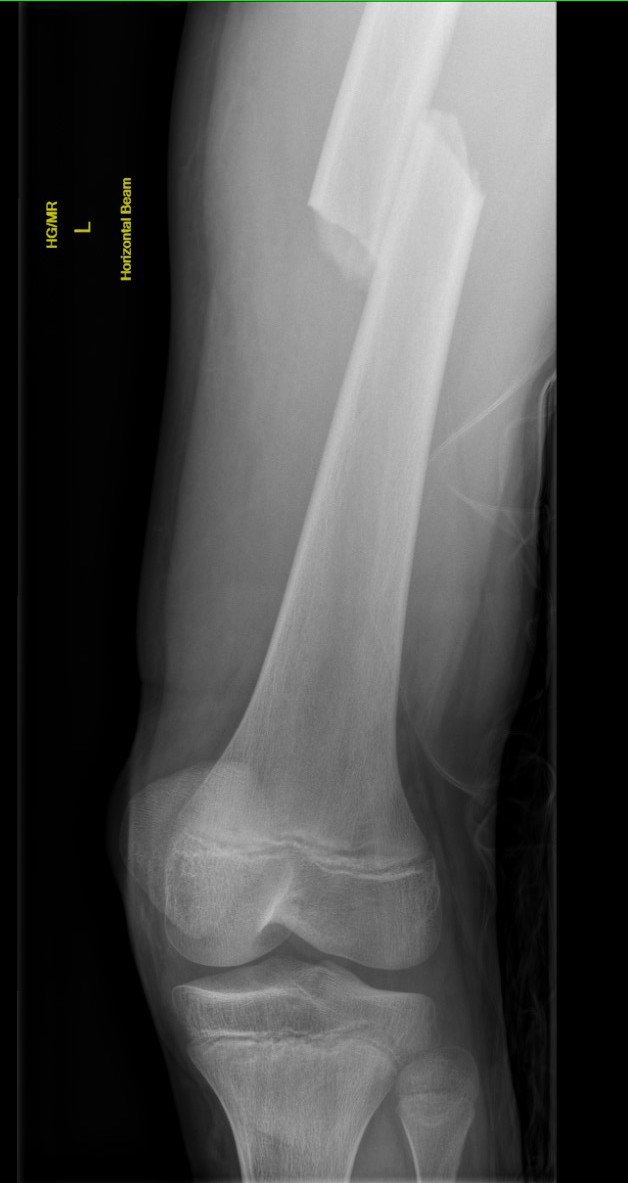

Management 12 years and over

Issues

Limited remodelling potential

Usually too heavy for flexible nails > 50 kg

Risk of AVN with standard pirformis entry nails

Options

Plate - incidence of refracture with plate removal

Lateral entry trans-trochanteric adolescent femoral nail

Adolescent Lateral entry Femoral Nail (ALFN)

AVN

Keeler et al. J Paediatr Orthop 2009

- 80 femoral fractures treated with lateral entry femoral nails

- no AVN

- no malunion or nonunion

MacNeil et al. J Paediatr Orthop 2011

- systematic review of risk of AVN after used of rigid locking nails

- piriformis fossa AVN rate 2%

- tip greater trochanter AVN rate 1.4%

- lateral entry / trans-trochanter AVN rate 0%